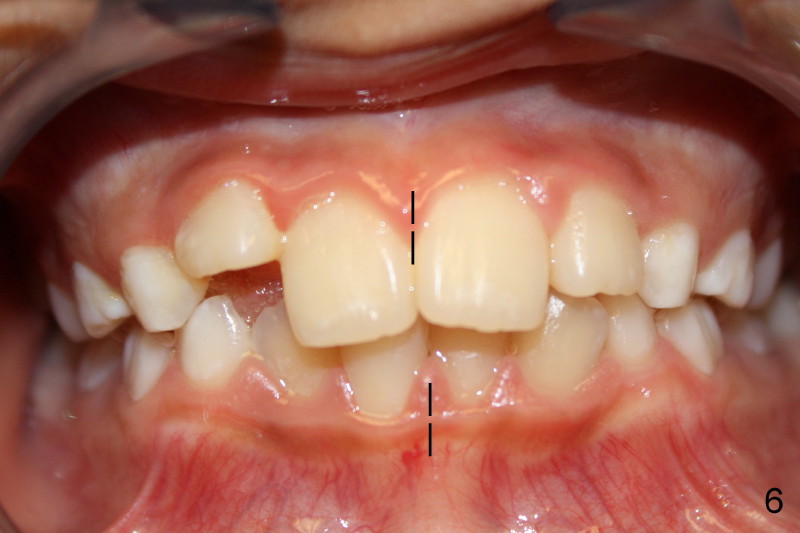

Panramic X-ray was taken when Edward was 6 years 5 months old (Fig.1). His parents and he himself found that the upper right lateral did not erupt at the age of 9 years 2 months (Fig.2-4: *). Gingivectomy was performed using soft tissue laser to expose the incisal edge of the lateral. Five months later, the lateral has erupted partially (Fig.5-8), but the family is concerned about the cosmetic issue. It appears that the upper midline has shifted to the right (Fig.6). Periapical film is planned to take to confirm the relationship between the canine and the lateral.

With all of the information presented above, early orthodontic intervention should be done now?

Appears that #7 is short a little room, therefore mechanically obstructed. Solution: make room! How? Slenderize the adjacent primary canine, extract C and H, or mild expansion. Tim Shaughnessy, DDS 11/22/2012